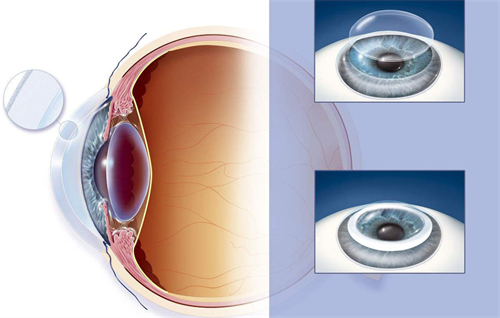

白内障手术是一种非常常见且安心的眼科手术,通常采用超声乳化技术将模糊的晶状体取出,然后植入人工晶状体以改善眼部视力。